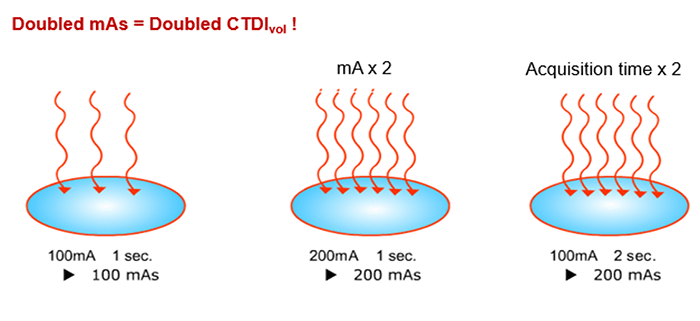

Influence of mAs

CTDIvol is directly proportional to the tube Current and acquisition time. mAs also affects patient dosage. It determines the total number of electrons and only the quantity of the photons is affected by a change in mAs. When mAs is selected, remember that longer scan times will require longer tube cooling and can cause an increase in patient motion. But an increase in scan rotation time will result in better resolution.

The increase of mA and kVp will improve the signal-to-noise ratio but also increase the dose to the patient. Remember, doubling the mAs will increase the CTDIvol.